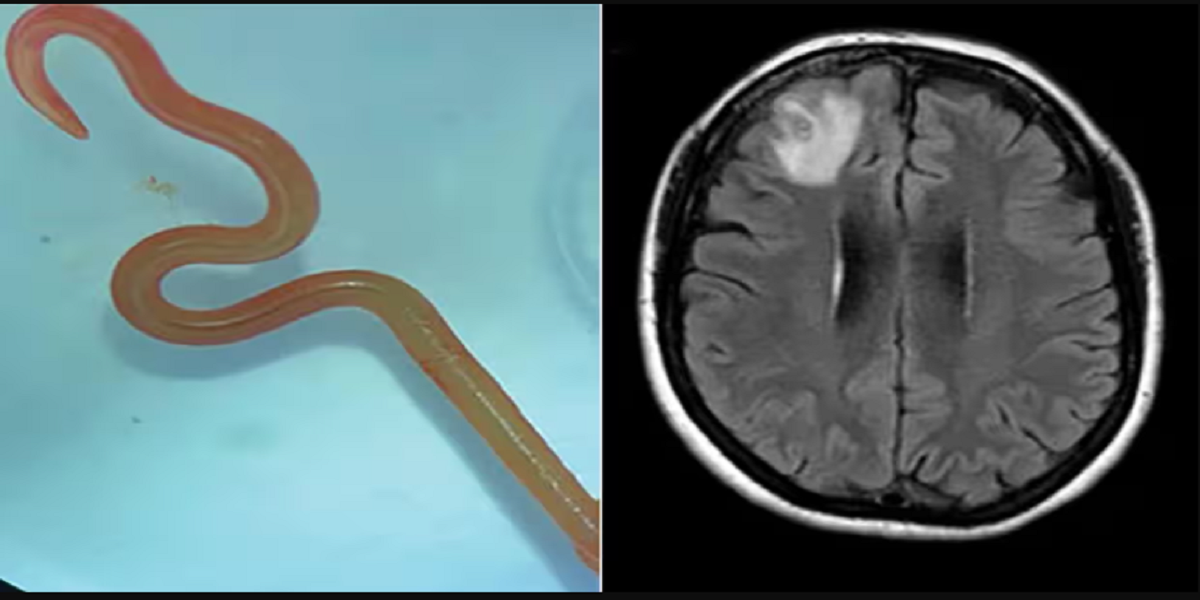

Neurokirurgen, Dr. Hari Priya Bandi, havde trukket en 8 cm lang parasitisk rundorm fra sin patient, hvilket fik hende til at ringe til Senanayake og andre hospitalskolleger for at få råd om, hvad hun så skulle gøre.

I 2022 inkluderede hendes symptomer også glemsomhed og depression, hvilket førte til en henvisning til Canberra hospital. En MR-scanning af hendes hjerne afslørede abnormiteter, der krævede operation.

“Canberra er et lille sted, så vi sendte ormen, som stadig var i live, direkte til laboratoriet hos en CSIRO-forsker, som er meget erfaren med parasitter,” sagde Senanayake. “Han kiggede bare på det og sagde: ‘Åh min gud, det her er Ophidascaris robertsi’.”